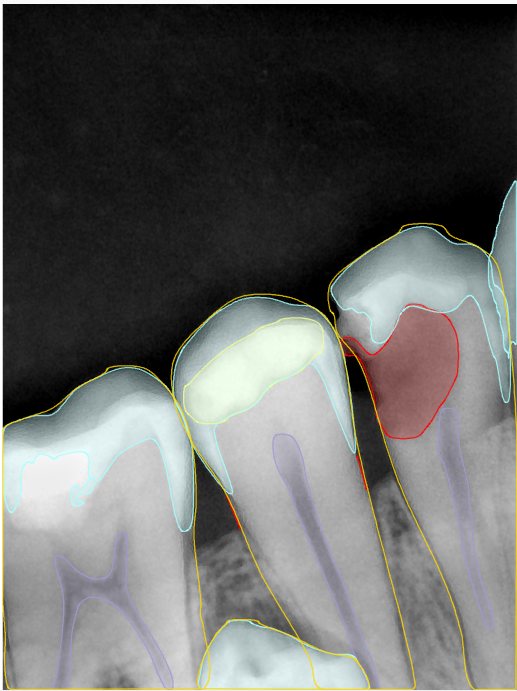

第二版算法问题测试

| 第一版 | 第二版 | 是否解决 | |

|---|---|---|---|

![]() | ![]() ![]() 边角识别有问题 龋齿识别不全 牙髓识别不全 | ![]() | 解决 |

![]() | ![]() 边角识别有问题 识别信息有误 自查(牙冠识别不全) | ![]() | 解决 |

![]() | ![]() ![]() 边角识别有误 大范围填充识别遗漏 | ![]() | 解决 |

![]() | ![]() 识别信息不全 | ![]() | 解决 |

![]() | ![]() ![]() 边角问题 牙胶识别不全 牙冠识别不全 | ![]() | 解决 |

![]() 换图片 | ![]() | ![]() 牙冠部分稍微白了一些就识别成小范围修补,部分判断异常 | 部分解决,修复类略敏感,牙冠部分稍微白了一些就识别成小范围修补,部分判断异常。 |

![]() | ![]() ![]() 牙冠识别不全 牙髓不全 根尖炎龋齿识别有误 | ![]() | 解决 |

![]() | ![]() | ![]() | 解决 |

![]() 换图片 | ![]() | ![]() | 解决 |

![]() | ![]() 牙冠识别有误 | ![]() | 解决 |

![]() 换图片 | ![]() ![]() 边角识别有误 | ![]() 修复类敏感 | 部分解决,图像过白,导致修复类判断异常。 |

![]() 换图片 | ![]() 牙冠识别不全 | ![]() 修复类敏感 | 部分解决,图像过白,导致修复类判断异常 |

结论:修复类出现了不鲁棒的情况,后续需要加入轮廓的扩充数据进行增强。